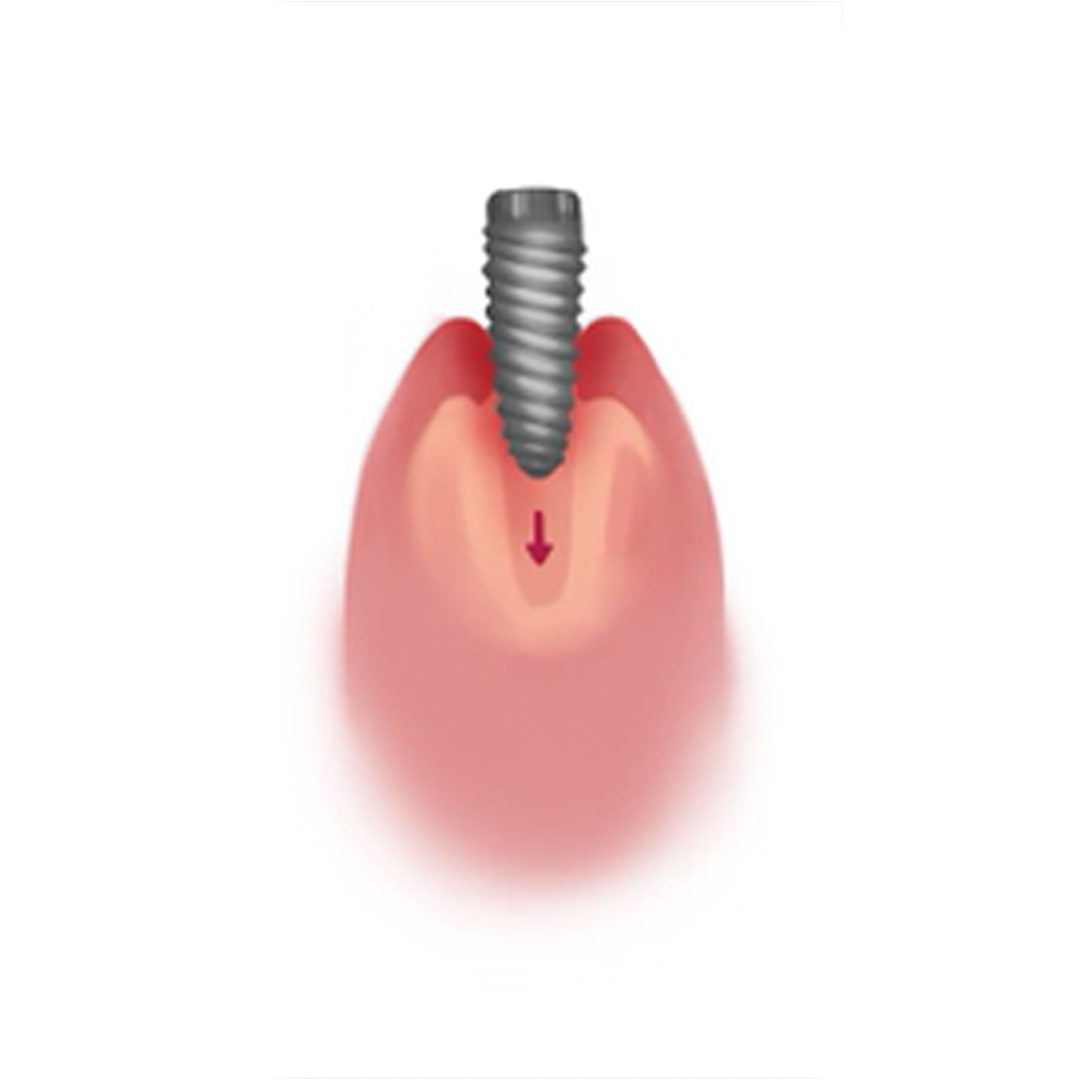

2. Osseointegration

The implant fixture is left to recover and fuse to the surrounding jawbone.

4. Healing & Osseointegration

It is normal to experience inflammation or/and sensitivity after the surgical procedure and your dentist can recommend some pain relieving medication. It is generally recommended that you eat soft foods while recuperating.

Before the final prosthesis (crown, bridge or denture) can be permanently cemented on the fixture, the dental implant fixture will need to osseointegrate with the jawbone. Bone cells in the jaw attach themselves directly on the titanium surface, permanently locking the dental implant fixture into the jawbone. The osseointegration process can take up to 6 months to complete.

The long-term success of any dental implant is highly reliant on osseointegration. As the failure to osseointegrate, will result in a failure of the implant procedure.

4. Healing & Osseointegration

It is normal to experience inflammation or/and sensitivity after the surgical procedure and your dentist can recommend some pain-relieving medication. It is generally recommended that you eat soft foods while recuperating.

Before the final prosthesis (crown, bridge or denture) can be permanently cemented on the fixture, the dental implant fixture will need to osseointegrate with the jawbone. Bone cells in the jaw attach themselves directly on the titanium surface, permanently locking the dental implant fixture into the jawbone. The osseointegration process can take up to 6 months to complete.

The long-term success of any dental implant is highly reliant on osseointegration. As the failure to osseointegrate will result in a failure of the implant procedure.